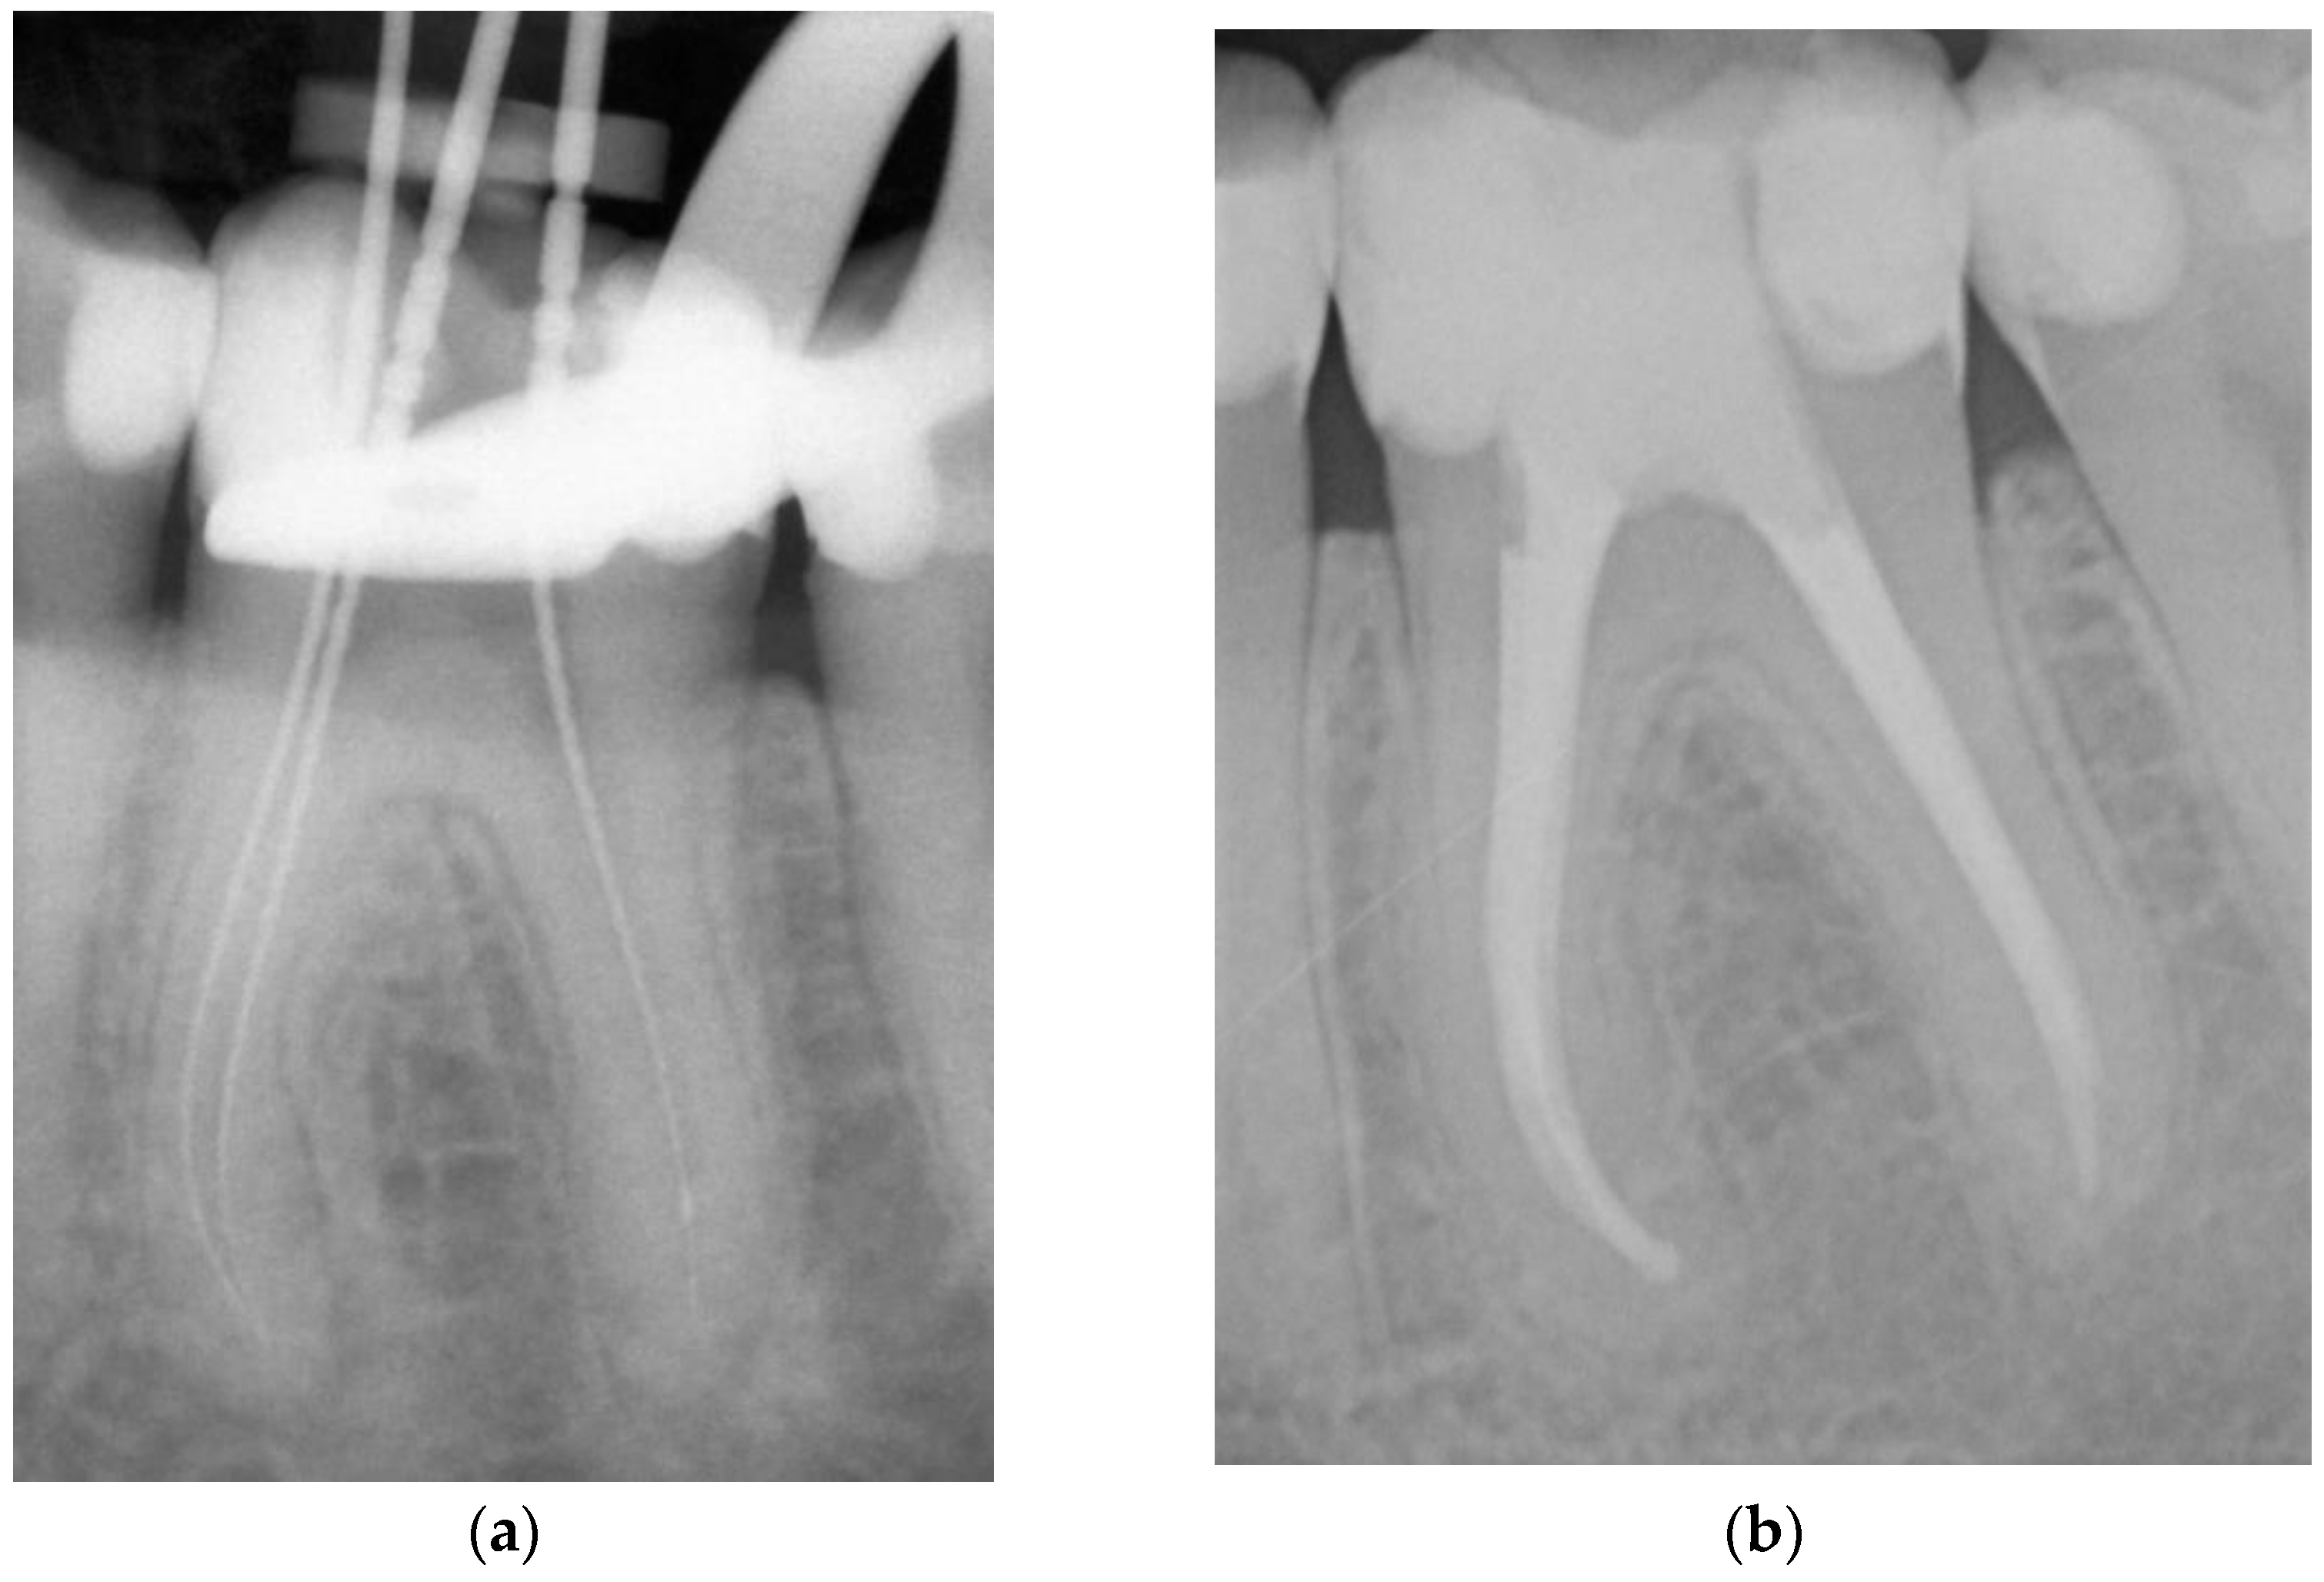

- Adhesive obturation using the continuous wave of condensation technique with Resilon® (CWR) (Figure 1).

Figure 1. Representative example of root canal filling with Resilon® using the continuous wave of condensation technique (CWR); working length radiograph of tooth 36 (a); 6-year follow-up radiograph showing complete apical healing (b). - Matching-taper single-cone obturation with gutta-percha and the epoxy-resin-based sealer AH Plus® (SCGP) (Figure 2).